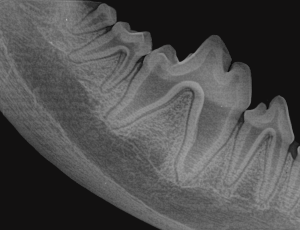

Canine Full Mouth Radiograph Example